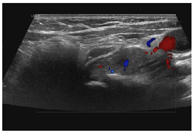

入院后行甲状腺超声示甲状腺左叶上、下极深方甲状旁腺区见2个囊实性结节,大小分别为2.9cm×1.4cm×1.1cm、2.3cm×1.4cm×1.2cm,均形态规则,边界清晰,CDFI:内见较丰富血流信号(图1,图2,图3,图4)。行甲状旁腺融合显像(显像剂:99Tcm-MIBI)示甲状腺左叶上极后上方见结节样显像剂浓聚灶,相应CT层面示椭圆形软组织密度影,边界清,大小约27.6mm×18.2mm×16.0mm。CT另见甲状腺左叶下极后下方一椭圆形软组织密度影,边界较清,大小约25mm×13.7mm×12.5mm,相应ECT层面未见显像剂摄取(图5,图6)。行嗜铬细胞瘤融合成像(显像剂:131I-MIBG)示颈部及腹部可见显像剂摄取病灶(图7,图8)。

超声图像中左侧甲状旁腺区2枚囊实性结节形态、回声、位置及血流均相似,结合实验室检查及临床病史,均提示为甲状旁腺腺瘤,但甲状旁腺融合成像仅支持甲状腺左叶上极后方结节为甲状旁腺腺瘤。甲状腺左叶下极后方结节无99Tcm-MIBI显像剂摄取,但有131I-MIBG高摄取,故综合以上考虑甲状腺左叶上极后方结节为甲状旁腺腺瘤,左叶下极后方结节为副神经节瘤。